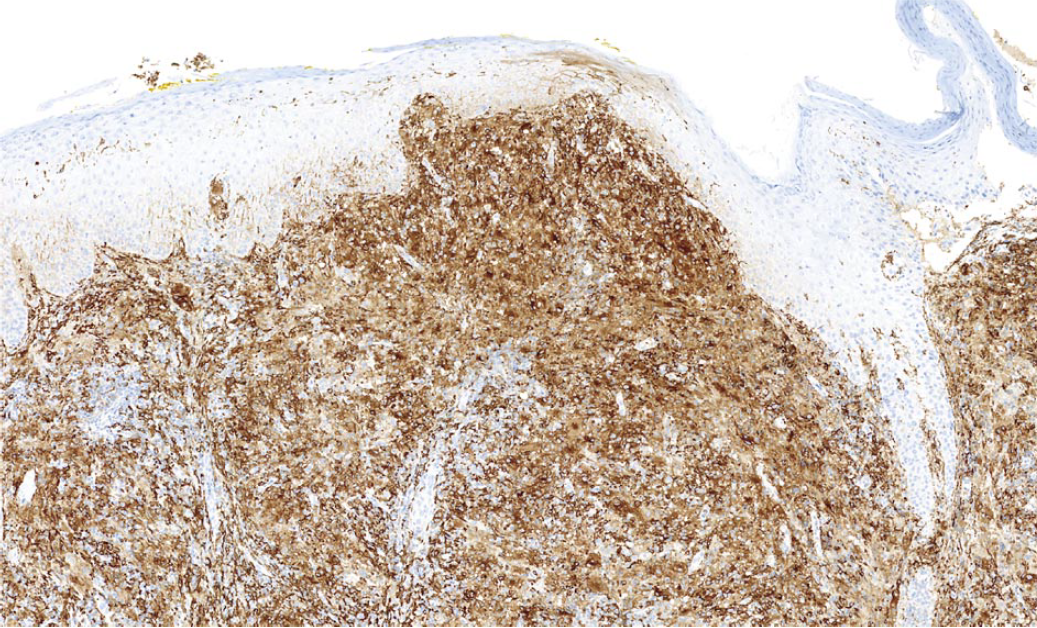

В октябре 2019 г. у мужчины 56 лет появилось опухолевидное образование на коже левой височной области. Через 3 нед опухоль радикально удалена. При гистологическом исследовании удаленного образования выявлена фиброзно-жировая ткань с хроническим гранулирующим воспалением. В течение 2 нед в зоне послеоперационной раны возобновился рост опухоли с появлением сливающихся папулезных высыпаний, которые распространились на кожу левой половины лица и волосистую часть головы. При повторном гистологическом исследовании в дерме обнаружился диффузный инфильтрат, состоящий преимущественно из гистиоцитов крупных размеров, гигантских клеток, небольшого количества плазматических клеток, скоплений лимфоцитов (рис. 1). При ИГХ-исследовании клетки гистиоцитарного ряда экспрессировали S100 (рис. 2), CD68, СD163 (рис. 3) и были негативны к фактору XIIIa, CD1a, CD123. При реакции с S100 визуализировались явления эмпериополеза (рис. 4). Таким образом, гистологические изменения и иммунофенотип клеток гистиоцитарного ряда соответствовали кожной форме БРД.

Рис. 2. Экспрессия клетками гистиоцитарного ряда S100.

Fig. 2. Expression of S100 by the histiocytic cells.